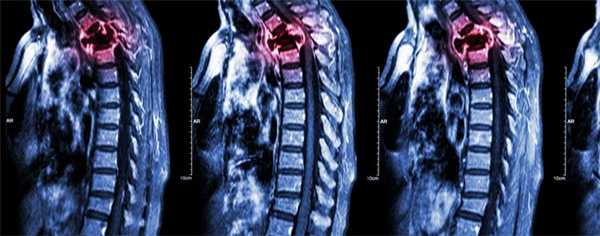

Метастазы в позвоночник

Метастазы в позвоночник – вторичное злокачественное поражение позвоночного столба, возникающее при миграции опухолевых клеток из очага, расположенного в другом органе. Проявляются болями, нарушениями чувствительности и движений, парезами, параличами, тазовыми расстройствами, гиперкальциемией и патологическими переломами. Диагноз «метастазы в позвоночник» устанавливают с учетом анамнеза, общего и неврологического осмотра, рентгенографии позвоночника, КТ позвоночника и других диагностических процедур. Лечение – химиопрепараты, радиотерапия, гормональная терапия, ламинэктомия, стабилизирующая операция.

Метастазы в позвоночник – вторичные очаги злокачественной опухоли другой локализации, поражающие позвонки и близлежащие анатомические структуры. Являются самым распространенным вторичным злокачественным поражением скелета. Составляют 13% от общего количества онкологических заболеваний. Встречаются чаще первичных неоплазий позвоночного столба. В 80% случаев метастазы в позвоночник диагностируются при раке легких, раке молочной железы и предстательной железы. Нередко обнаруживаются при саркомах и лимфомах. Может поражаться любой отдел позвоночника. Чаще страдают грудной и поясничный отделы, в шейном отделе метастазы в позвоночник выявляются относительно редко. Прогноз неблагоприятный. Лечение проводят специалисты в сфере онкологии и вертебрологии.

О наличии онкологического заболевания свидетельствует положительный анализ крови на онкомаркеры. На начальном этапе диагностики больным с подозрением на метастазы в позвоночник назначают рентгенографию позвоночника. На ранних стадиях метастазирования рентгенологические признаки поражения позвонков могут отсутствовать, поэтому при отрицательном результате исследования пациентов с подозрением на метастазы в позвоночник направляют на сцинтиграфию, КТ и МРТ позвоночника. Для выявления первичной неоплазии и вторичных очагов проводят УЗИ органов брюшной полости, рентгенографию органов грудной клетки, маммографию и другие диагностические процедуры. Дифференциальную диагностику метастазов в позвоночник осуществляют с сосудистыми поражениями, последствиями воспалительных заболеваний, вторичной демиелинизацией и первичными неоплазиями позвоночного столба.